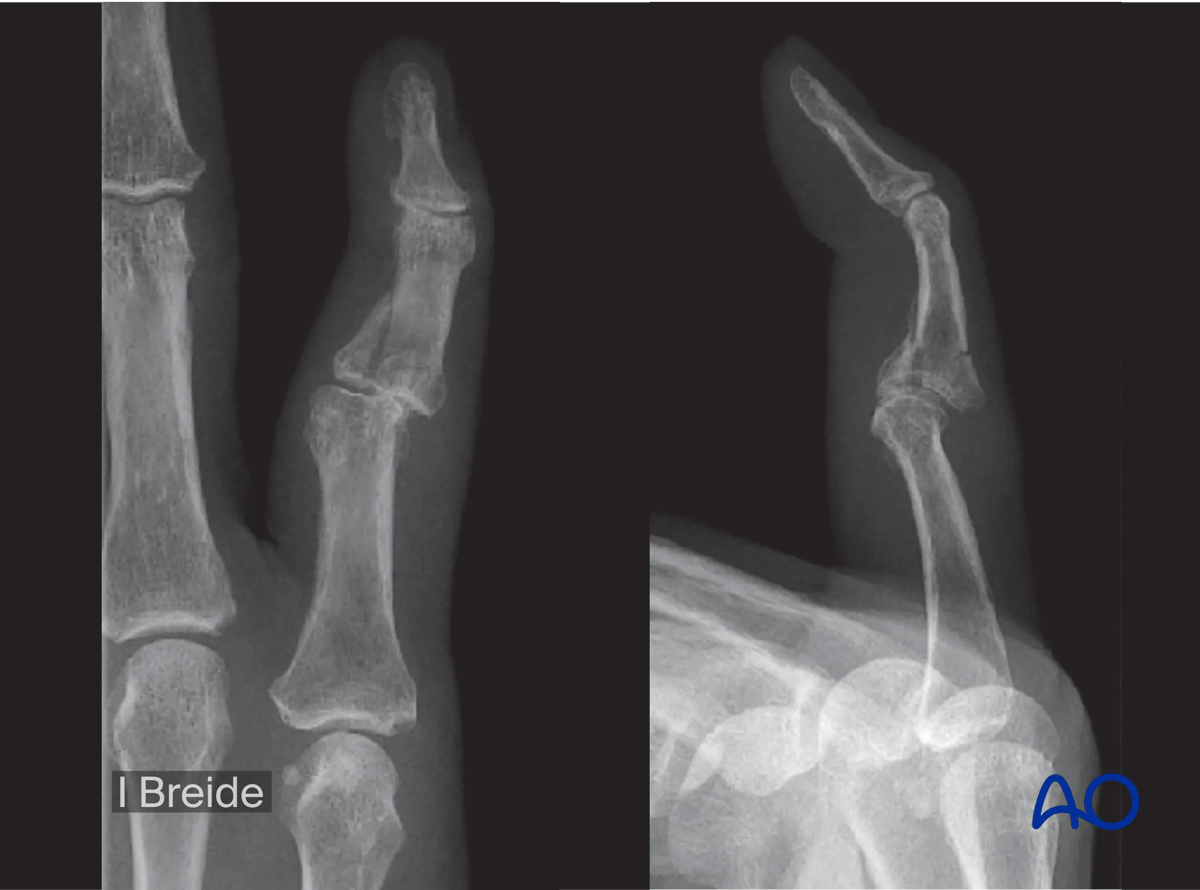

AP and lateral x-ray of a pilon fracture of the 5th middle phalangeal base.